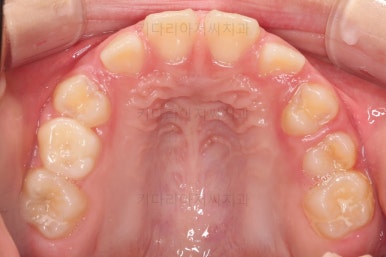

치료 22개월 째 종료시점의 사진입니다.

전후 비교해 볼게요.

교합도 좋아졌고 앞니 관계(반대교합, 개방교합)도 개선이 잘 되었어요.